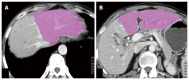

Hilar cholangiocarcinoma is a common malignant tumor of the biliary tree. It has poor prognosis with very low 5-year survival rates. Various imaging modalities are available for detection and staging of the hilar cholangiocarcinoma. Although ultrasonography is the initial investigation of choice, imaging with contrast enhanced computed tomography scan or magnetic resonance imaging is needed prior to management. Surgery is curative wherever possible. Radiological interventions play a role in operable patients in the form of biliary drainage and/or portal vein embolization. In inoperable cases, palliative interventions include biliary drainage, biliary stenting and intra-biliary palliative treatment techniques. Complete knowledge of application of various imaging modalities available and about the possible radiological interventions is important for a radiologist to play a critical role in appropriate management of such patients.We review the various imaging techniques and appearances of hilar cholangiocarcinoma and the possible radiological interventions.